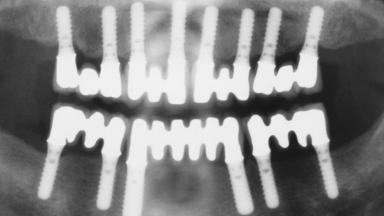

Immediate Loading of Eight Implants in the Maxilla and Six Implants in the Mandible and Final Restoration with Three-Unit and Four-Unit FDPs

Extensive scientific evidence has confirmed that immediately loaded implants with fixed full-arch provisional restorations can osseointegrate with success rates similar to conventionally or delayed loaded implants. A number of immediate-provisionalization techniques for edentulous jaws have been described. Some protocols differ when it comes to prefabricated provisional templates versus complete denture conversion; intrasurgical impressions versus direct relining; and cemented versus screw-retained provisional restorations. In this context, complete-denture conversion has been proposed for either intrasurgical impressions or direct relining. Another possibility is the utilization of a prefabricated provisional to be adapted either in the mouth (by direct relining) or in the laboratory (on a working model obtained from an intrasurgical impression).

# of Implants 14

Type of Implants One-Piece

Defining Characteristics Fully edentulous upper jaw to be rehabilitated with four or more implants

Modality 6+ implants with immediate loading

Defining Characteristics Fully edentulous upper jaw to be rehabilitated with an implant-borne fixed dental prosthesis

Loading Protocol Immediate